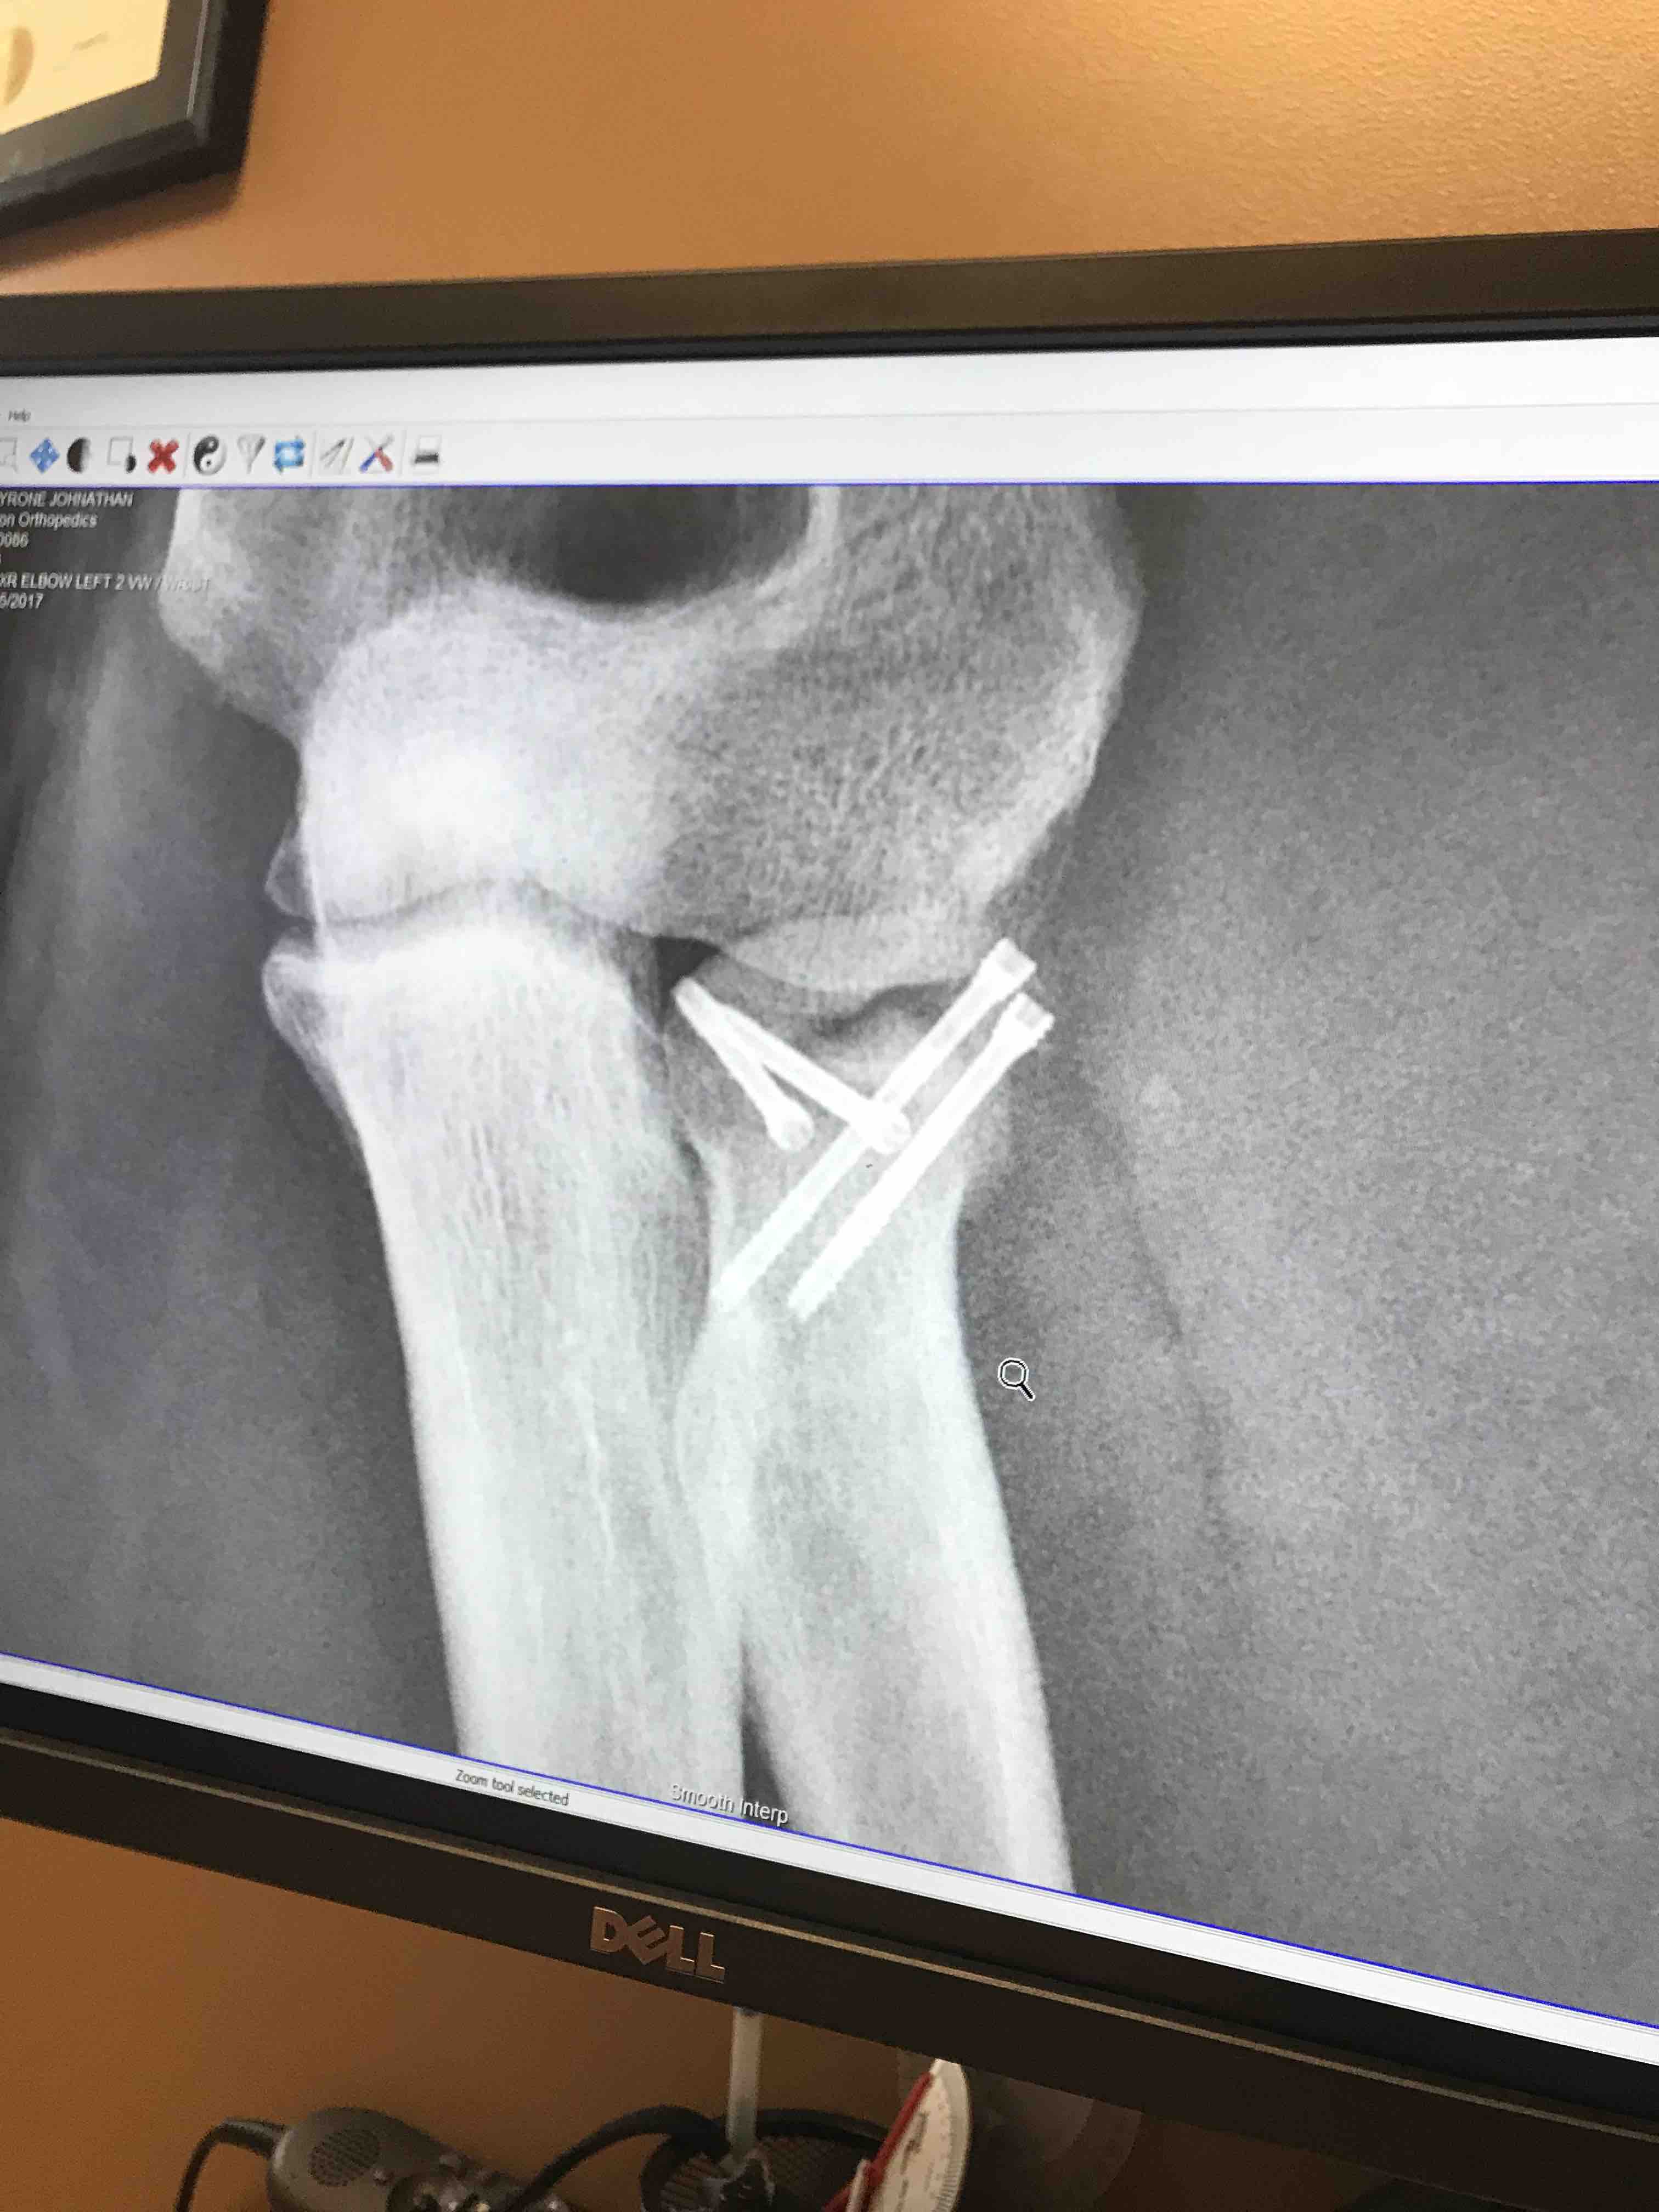

Tyrone was in a very serious Hit & Run accident on September 15th, he was riding his motorcycle to work, someone cut him off, clipped his bike and took off leaving him lying in the middle of the road.

Hes alive "Thank you Jesus" however his road to recovery will be long and arduious. Even with full coverage his medical expenses, co-pays, missed work, and upcoming physical therapy are going to be exhorbatant.